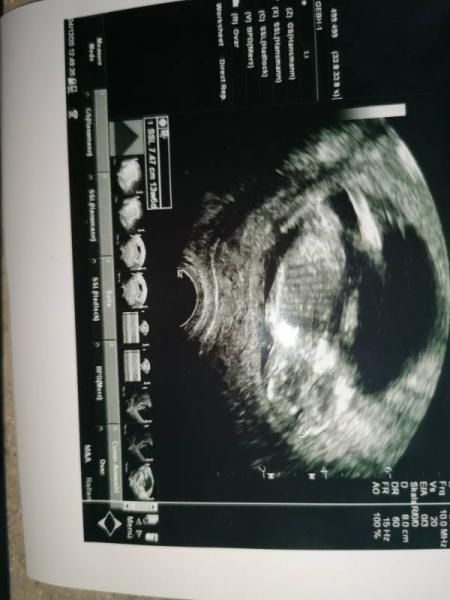

Hi war heute beim FA, bin aktuell in der 14.ssw. Könnt ihr das Geschlecht erkennen?

Bild zu Erkennt ihr das Geschlecht? - Forum für Juni - Mamis